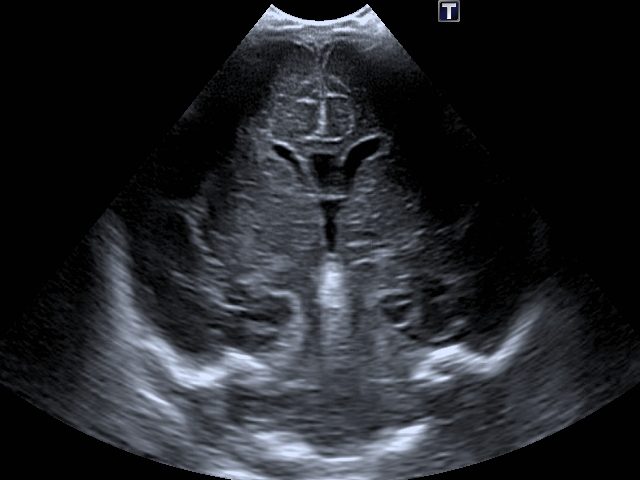

Ultraschall der Nieren

Wir empfehlen allen Eltern eine Ultraschalluntersuchung der Nieren ihres Neugeborenen.

Fehlbildungen der Nieren zählen zu den häufigsten angeborenen Veränderungen und lassen sich durch eine frühzeitige Untersuchung zuverlässig erkennen.